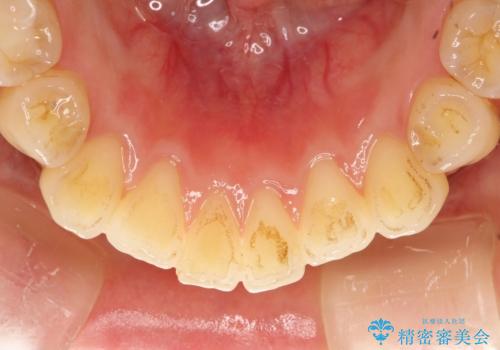

- 全体の歯にうっすらと茶渋によるステインが見られます。

よく見ると歯自体はあまり黄色くないので、ステインによって歯が黄色く見えてしまっています。

PMTCというクリーニングを行うことでステインは除去できるので、今回はPMTC(エアフロー)の60分コースにて全体のクリーニングを行いました。